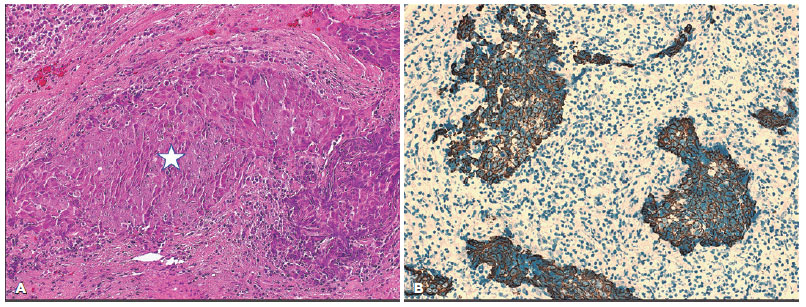

In the second part of our analysis, based on the histopathological classification and comparison according to the WHO grading, we initially compared the WHO grading between the same two groups in 35 patients, and more than half of the patients in both groups were classified as WHO III (55.6% and 57.7%, respectively) with no statistically significant difference (Table 3). The outcome was available for only 24 of the 35 patients, and when we correlated the outcome of 23 of 24 patients (1 patient with WHO grade I was excluded) in relation to WHO grades II (Figure 3) versus III irrespective of the group to which they belong in Table 4, there was no statistically significant difference in the outcome (p=0.094).